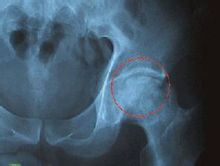

X线检查